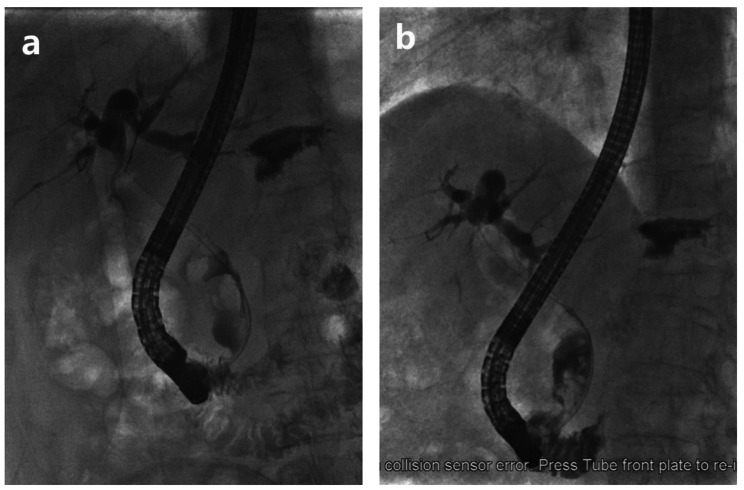

We compared the bile duct stone diameter, ERCP procedure time, adverse event rate and length of hospital stay during two ERCPs for all 64 patients in group B with their own controls (Table 3). The results indicated that after stent drainage, the diameter of CBD stones significantly decreased (1.59 ± 0.544 cm vs. 1.95 ± 0.543 cm, P < 0.001) (Fig. 2), and in one patient, the CBD stones completely disappeared during the second ERCP. The ERCP procedure time of the second ERCP was significantly longer than that of the first ERCP (36.70 ± 16.411 min vs. 20.48 ± 11.975 min, P < 0.001). There was no significant difference in the length of hospital stay (10.11 ± 2.885 vs. 9.47 ± 1.681, P = 0.132) or the overall ERCP-related adverse event rate (18.8% vs. 10.9%, P = 0.214) between the two ERCP procedures. While the incidence of PEP of the second ERCP was significantly lower than that of the first ERCP (3.1% vs. 12.5%, P = 0.048). No bile duct stent displacement was found in any patients in group B.